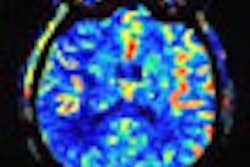

For the second question, researchers found four class IV stroke studies that evaluated a correlation between baseline DWI and PWI lesion volume and chronic lesion volume. One class II study assessed the correlation of baseline DWI and PWI lesion volume with clinical outcome. They also found two class II studies and one class III study to assess clinical and morphologic outcome.

In the class II stroke study, 115 of 631 patients (18%) had symptoms of posterior circulation ischemia. Of those 115 patients, 40 patients (34%) fulfilled the inclusion criteria with regard to the 24-hour time window and available imaging data. In all 40 patients, DWI detected an acute lesion corresponding to the patient's symptoms, while PWI detected a lesion in 16 patients.

Of the 100 patients enrolled in this class II study, 81 patients had interpretable MR measurements. Baseline DWI and PWI lesion volumes correlated with baseline NIHSS scores. Baseline DWI volume also correlated with follow-up lesion volume 12 weeks after the stroke.

Based on the results, the authors found "significant correlations" between lesion volumes and clinical measures, and suggested that the findings support the role of DWI "as a clinically meaningful surrogate marker in stroke clinical trials."